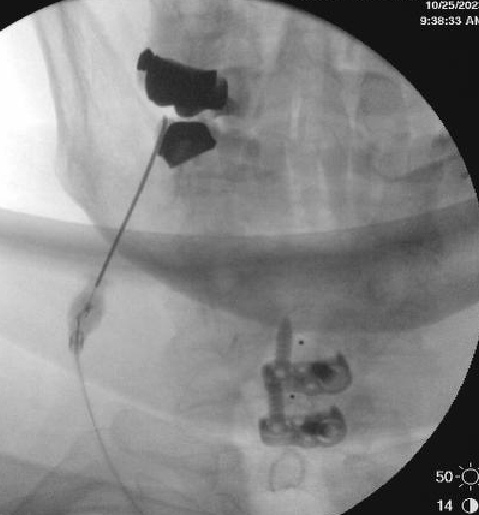

Nasty neuritis. This is 80 degrees 90 seconds.

These images look great. Sorry it happened? Steroid?

Lyrica Rx sent in, and we're starting it for chronic pain (and neuritis). She gets a shoulder scope in two weeks for a large RCT. I like antineuropathics (gabapentin 100mg HS or BID) perioperatively in general. I wish they were given 2 weeks before and after ALL orthopedic surgeries.

Dexamethasone given before RFA needles were removed.